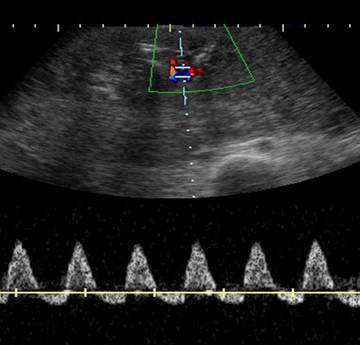

24歲孕婦,G3P0,妊娠38週,接受胎兒杜卜勒超音波檢查,結果如圖所示,檢查名稱為何?

詳解

登入後即可查看逐題解析與答題

【109-1 醫學(六) 第57題】承上題,最可能的檢查結果為下列何者?

破題關鍵

在胎兒臍動脈血流檢查中,舒張末期血流逆轉 (reversed end-diastolic velocity) 是胎盤功能嚴重不足,胎兒處於極度危險的徵象。

選項拆解

登入查看完整詳解與互動作答